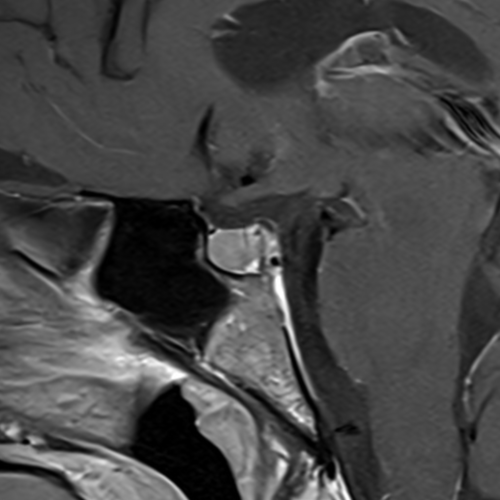

Cet examen est réalisé pour analyser l’hypophyse, la post hypophyse, l’anté hypophyse et le chiasma optique. Il est réalisé en cas d’hyperprolactinémie, de troubles visuels.

Cette examen permets d’analyser l’hypophyse (ante et post hypophyse), la tige pituitaire, le chiasma optique. Il permet de diagnostiquer les micro adénomes, macro adénomes, tumeurs des sinus caverneux.